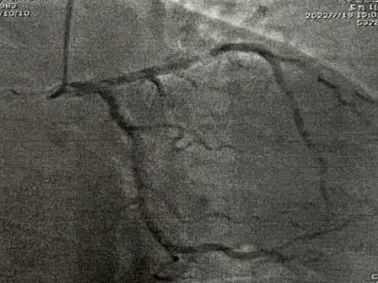

冠脉造影

冠脉硬化

LAD病变